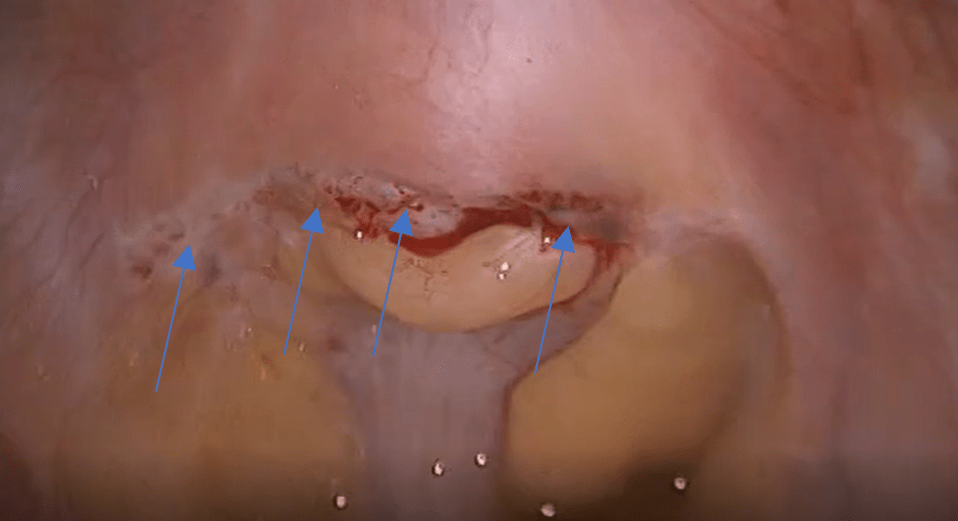

Endometriose profunda localizada no peritônio da região retrocervical, ligamentos útero sacros e assinaladas com setas azuis. Imagem de laparoscopia.

Endometriose Profunda

A endometriose profunda é definida quando a infiltração do tecido endometrial na superfície do peritônio é maior ou igual a 5 mm ou quando acomete outros órgãos na pelve, como o intestino, bexiga e vagina.

É o tipo mais importante de endometriose devido a intensidade dos sintomas que determina e a maior dificuldade no tratamento.

Os locais mais frequentemente acometidos em ordem decrescente para endometriose profunda são a região retrocervical, ligamento uterossacro, intestino, vagina, bexiga e ureter

Região Retrocervical

A endometriose retrocervical acomete cerca de 90% das mulheres com endometriose profunda, e portanto, é a forma mais comum da doença.

É definida quando localizada no atrás do colo uterino, ligamento uterossacro e a região do fundo de saco posterior. Esta lesão é a principal responsável pelos sintomas de cólica menstrual.